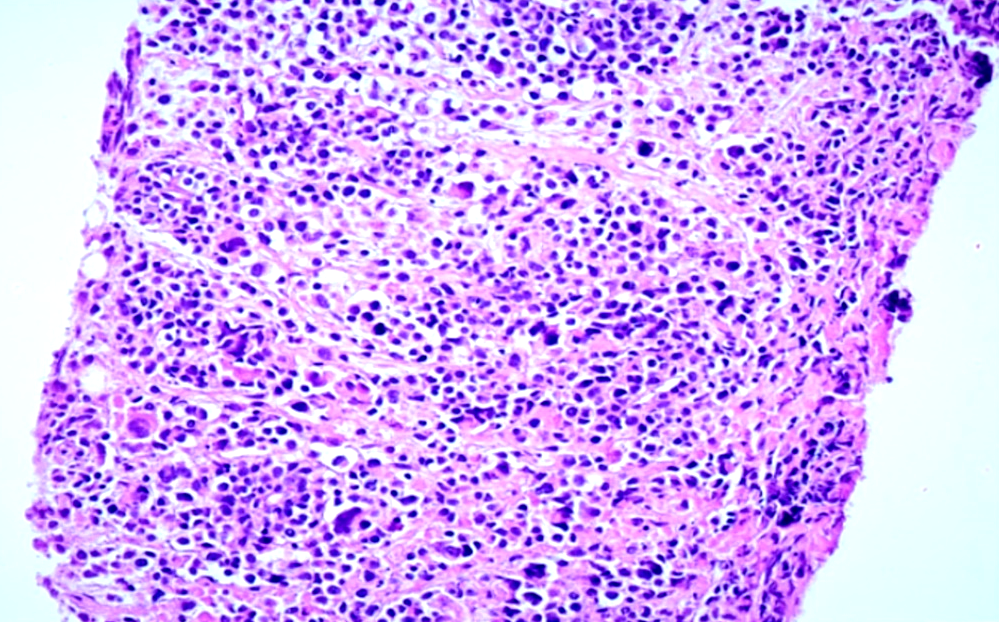

Se realizó una biopsia de la lesión tumoral a nivel del bulbo duodenal, cuyo estudio histopatológico informó la presencia de abundantes células linfoides grandes y atípicas (Fig. 1 - Ver imagen con la resolución original).